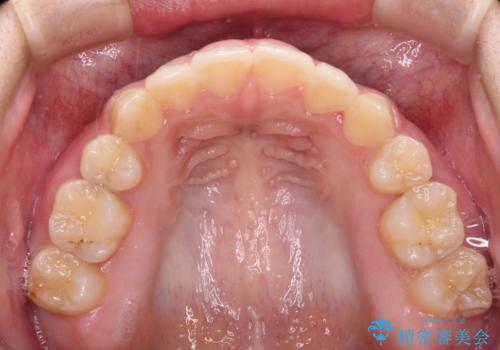

- 顕著な八重歯が気になるとのことで来院された患者様です。

インビザラインでの治療を希望されましたが、インビザライン単独では困難と判断されたため、補助装置や一部ワイヤー装置を用いて行うこととしました。

叢生が強いため、上下左右第一小臼歯4本を抜歯することとしました。

ワイヤー装置を用いた場合、一般的には2年程度で終了することを考えると、「移動量が多くなると治療期間が長くなる」というインビザライン矯正の最大の弱点が現れた治療となりました。